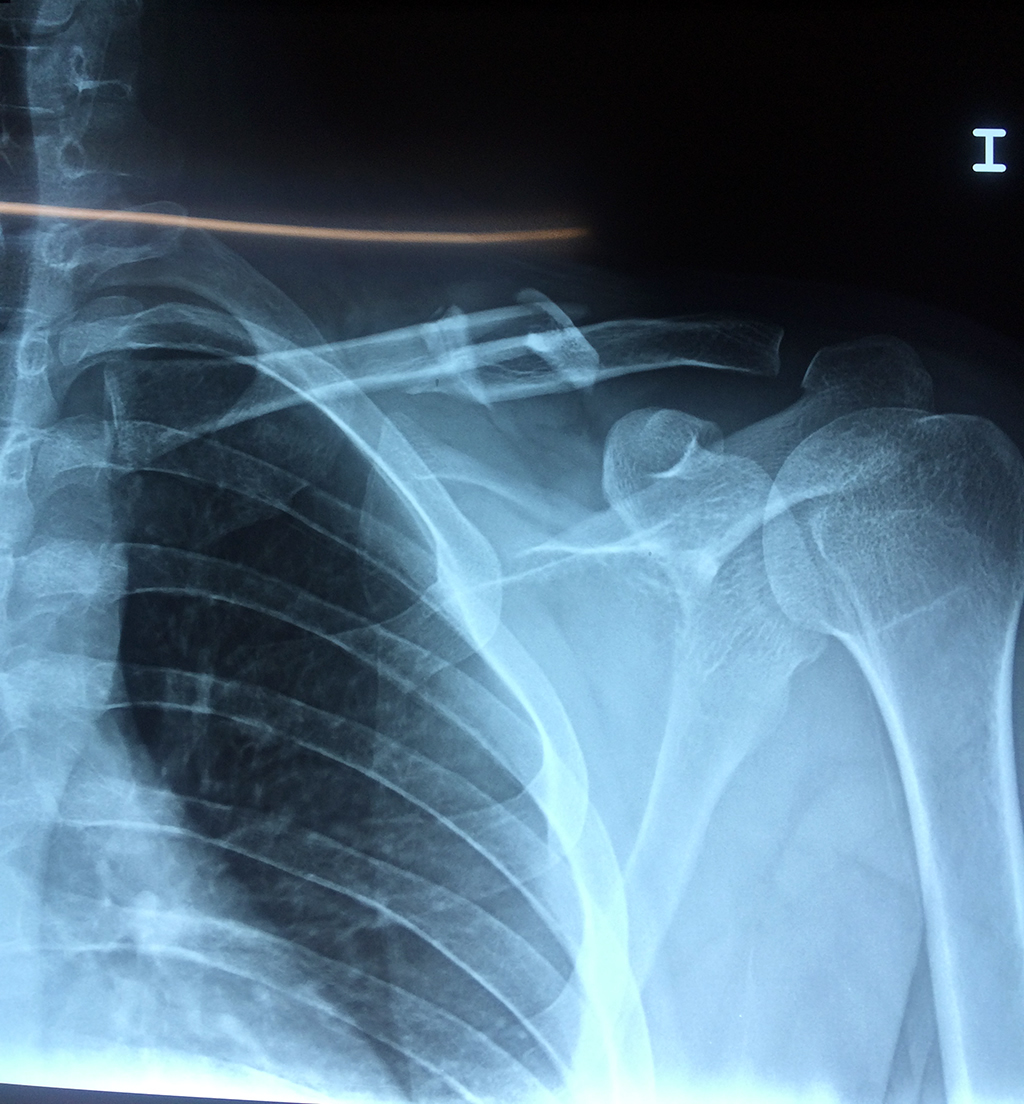

Calcaneo - Clavícula

La clavícula es un hueso largo, con forma de "S" itálica, situado en la parte anterosuperior del tórax. Junto con la escápula forman la cintura escapular. Se puede palpar por toda su longitud y se extiende del esternón al acromion de la escápula, siguiendo una dirección oblicua lateral y posterior.